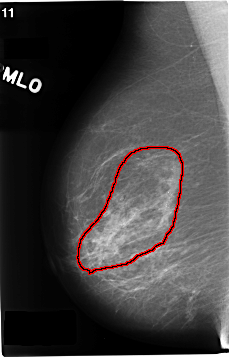

ics_version 1.0 filename C-0172-1 DATE_OF_STUDY 8 5 1996 PATIENT_AGE 70 FILM FILM_TYPE REGULAR DENSITY 2 DATE_DIGITIZED 12 3 1998 DIGITIZER LUMISYS LASER SEQUENCE LEFT_CC LINES 4760 PIXELS_PER_LINE 2616 BITS_PER_PIXEL 12 RESOLUTION 50 NON_OVERLAY LEFT_MLO LINES 4720 PIXELS_PER_LINE 2816 BITS_PER_PIXEL 12 RESOLUTION 50 NON_OVERLAY RIGHT_CC LINES 4696 PIXELS_PER_LINE 2680 BITS_PER_PIXEL 12 RESOLUTION 50 OVERLAY RIGHT_MLO LINES 4640 PIXELS_PER_LINE 2976 BITS_PER_PIXEL 12 RESOLUTION 50 OVERLAY |

FILE: C_0172_1.RIGHT_MLO.OVERLAY TOTAL_ABNORMALITIES 1 ABNORMALITY 1 LESION_TYPE CALCIFICATION TYPE PLEOMORPHIC DISTRIBUTION REGIONAL ASSESSMENT 5 SUBTLETY 5 PATHOLOGY MALIGNANT TOTAL_OUTLINES 1 BOUNDARY |